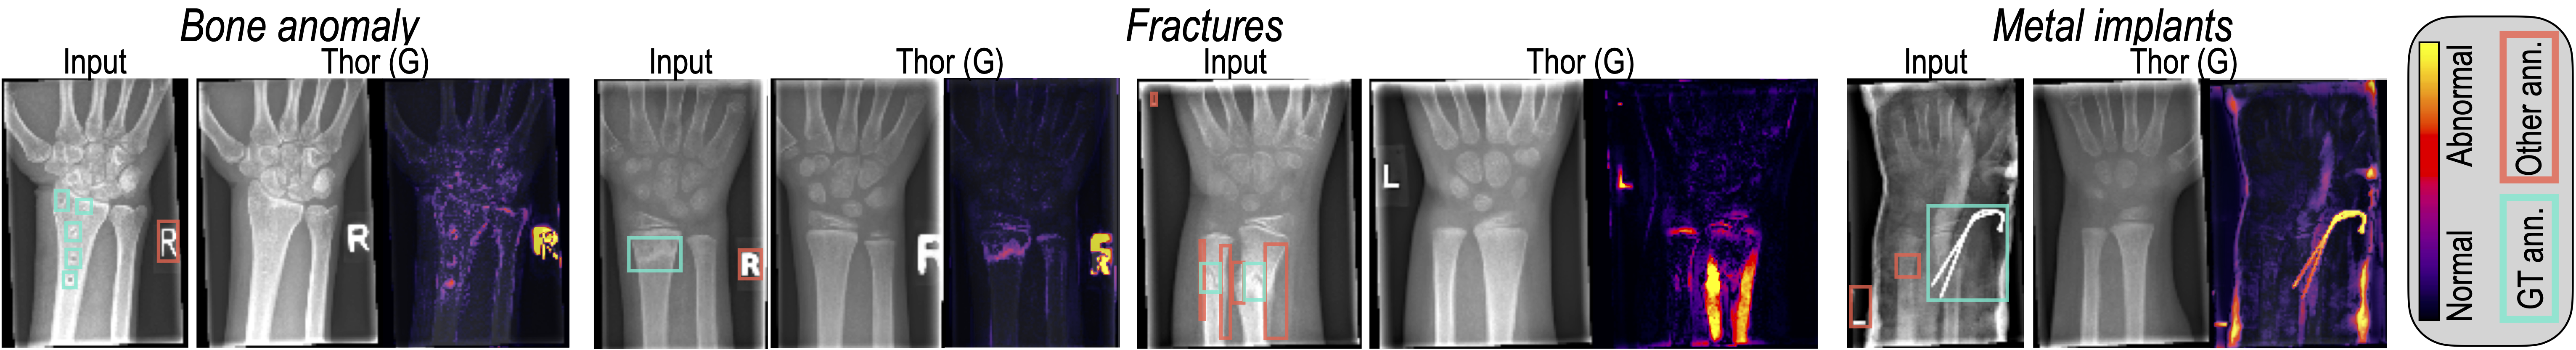

Results. Tab. 2 and Fig. 5 present both quantitative and qualitative outcomes. For this experiment, we concentrated on Gaussian noise, recognizing from prior analysis that Simplex noise lacks versatility for widespread anomaly detection applications. It tends to replicate anomalies dissimilar to its coarse patterns, such as bone anomalies, foreign bodies, and metal implants, as detailed in the supplementary materials. THOR outperforms SOTA diffusion models, considerably improving the number of anomalies detected by up to 65% in case of fractures and achieving almost perfect recall in detecting metal implants.

Refer to caption

Figure 5: Anomaly detection in pediatric wrist X-rays processed by THOR using Gaussian noise. False positives arise from unannotated non-pathological changes like unnatural bone positions following fractures or the presence of casts.